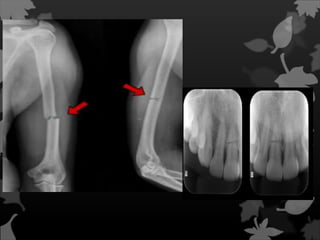

É uma fratura da ulna que afeta

a articulação com o rádio. Mais

precisamente, é uma fratura do

terço proximal da ulna com

deslocamento da cabeça do rádio.

Fratura de Galeazzi

Uma fratura de

Galeazzi é

uma fratura da região

distal do rádio com

ruptura da membrana

interóssea e da

ligação com a ulna,

com subluxação da

ulna.